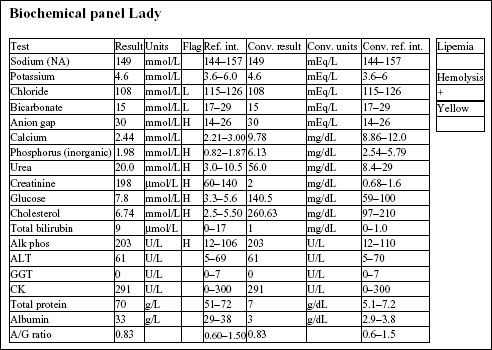

Lady, a 15-year-old F(s) Chihuahua X dog, had lethargy and a severe heart murmur.

The Hct, Hgb, and RBC count are all mildly increased, indicating erythrocytosis. Although the RDW is increased, this does not correlate with an increase in anisocytosis. The total solids are not increased. There is a mild neutrophilia, very mild left shift, lymphopenia, and mild monocytosis. The leukogram changes are consistent with stress (high levels of endogenous cortisol).

The chloride is decreased relative to the sodium, suggesting selective chloride loss, possibly from vomiting (not given in the history). There is a high anion gap metabolic acidosis, which may be due to decreased tissue perfusion. The mild azotemia (increased phosphorus, urea, and creatinine) is likely pre-renal from reduced renal perfusion, given the urine specific gravity (SG). Mild hyperglycemia and hypercholesterolemia are unlikely to be clinically significant. Mildly increased alkaline phosphatase (ALP) activity could be due to cholestasis or enzyme induction from chronic stress/elevated cortisol.

The urine SG indicates adequate renal function. Protein at 2+ could be significant; however, this could be better assessed by urine protein to creatinine ratio. Blood reaction appears to be due to mild hematuria. This is a free flow sample, so hematuria is unlikely to be iatrogenic (as seen with cystocentesis sampling), unless the bladder had been manually compressed to obtain the sample.

• The erythrocytosis is likely to be absolute and secondary to cardiac disease. EPO levels would be expected to be elevated because the erythrocytosis is a physiologic response to decreased arterial pO2 caused by heart failure.